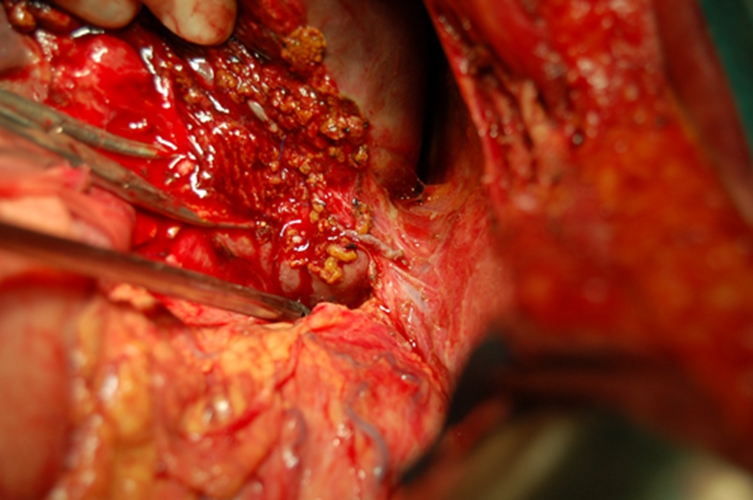

下段膽管癌